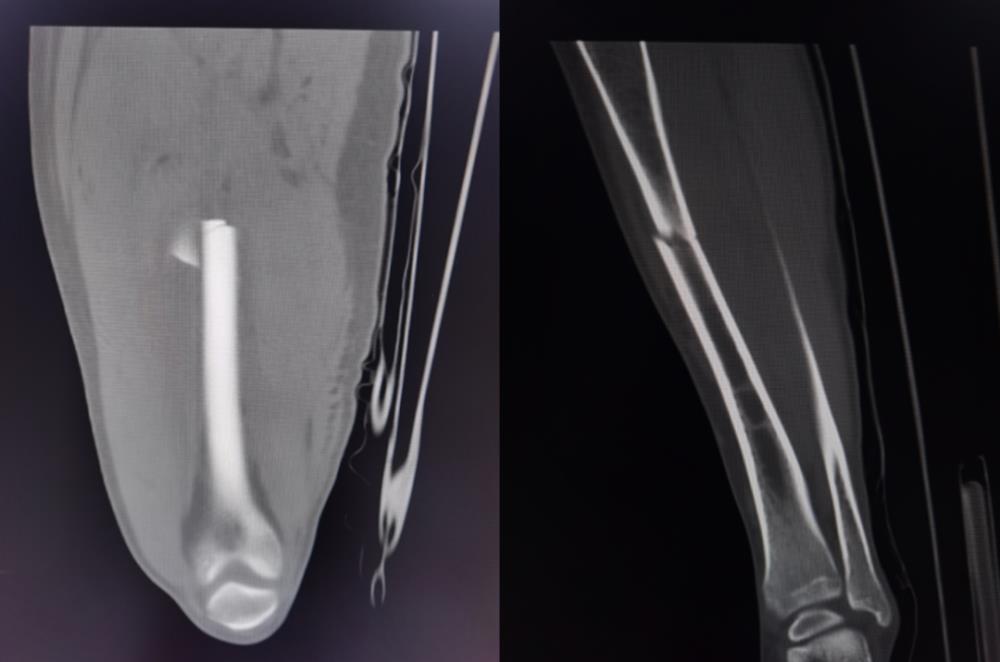

近日,我院收住了一名15岁因车祸骨折入院的患者,CT提示为右股骨干骨折、右胫骨上段骨折,本身这类患者在我院非常常见,但是他却出现了罕见的中风情况,情况非常凶险。

患者经ICU积极治疗后,在住院第4天完全清醒,言语流利,对答切题,肢体活动良好。由于病情危重,暂时无法行手术治疗,入院后行骨牵引固定,减轻骨折处疼痛。于住院第6天顺利转出普通病房。住院第11天,复查颅脑CT提示梗死病灶完全消失。病情稳定后于住院第17天行手术治疗,住院第31天顺利出院。

这里就得提到前面ICU钟瑜主任判断的脂肪栓塞综合征了。骨折是导致脂肪栓塞综合征最常见的病因。